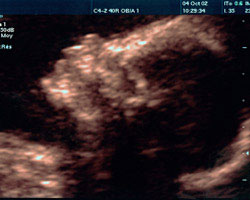

Em seguida, mostramos-te um vídeo no qual poderás observar um feto em movimento na 22ª semana, bem como a imagem de uma ecografia da mesma semana. Não percas!

Ecografia de 22 semanas